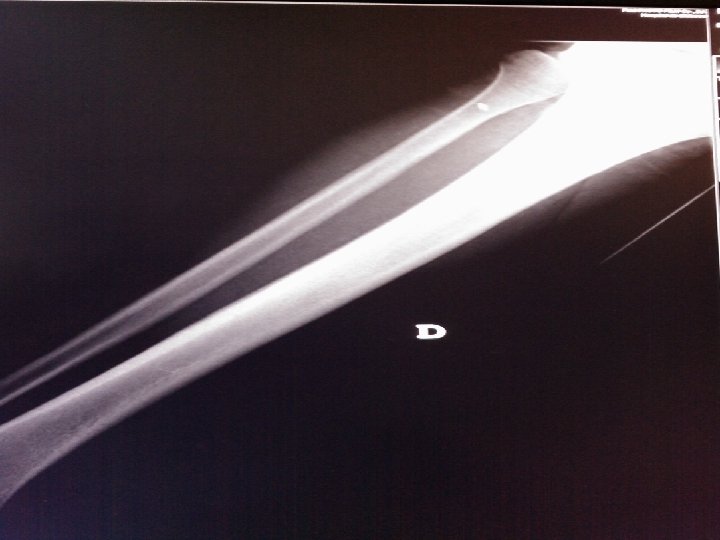

Tipo c: o Fx del peroné por encima de la sindesmosis o La Fx puede encontrarse en el 1/3 inferior, 1/3 medio de la diáfisis o a nivel del cuello del peroné(Fx de Maisonneuve) o Aumento de la posibilidad sobre todo en presencia de Fx maleolo interno

Juicio Diagnóstico: Fractura desplazada trans suprasindesmal maleolo peroné dcho.